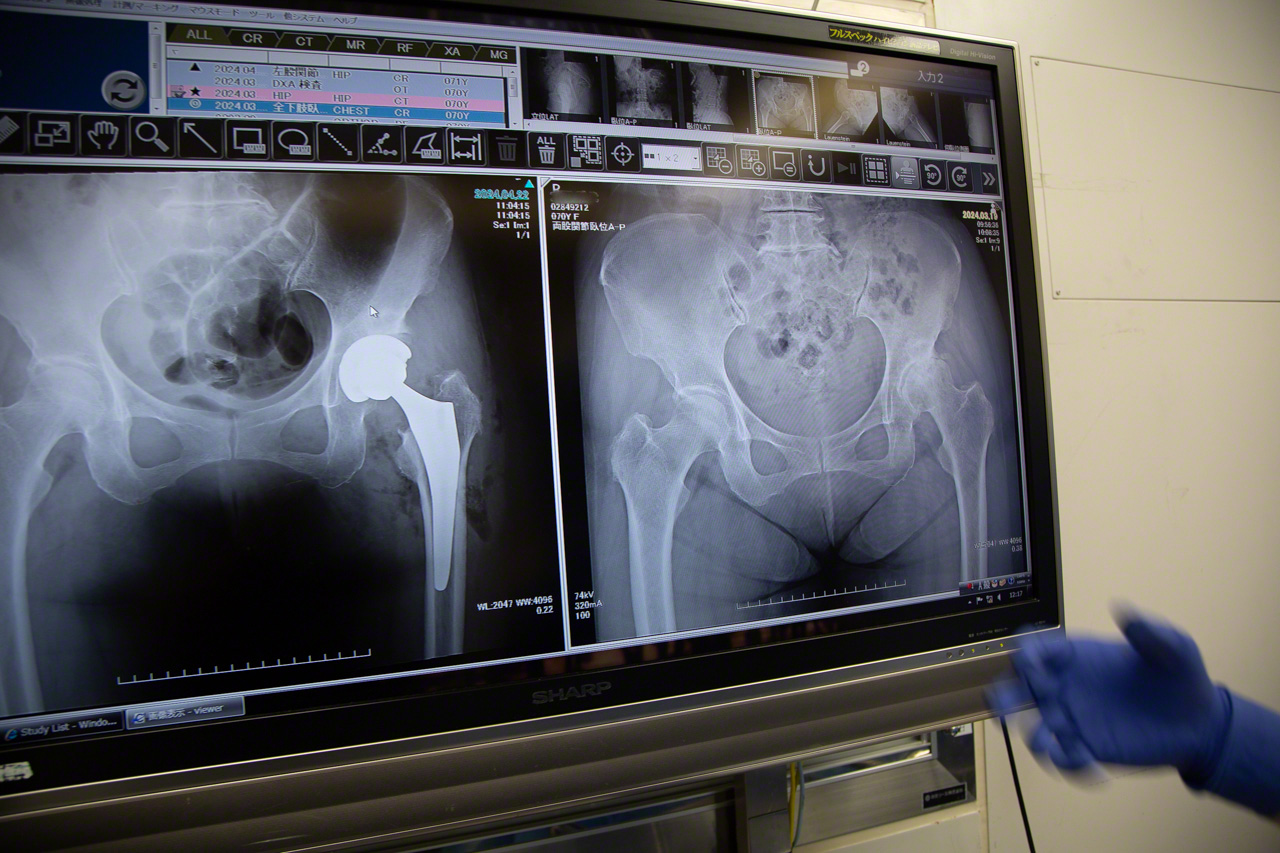

手术1周前,医生会聚集到叫“绘描室”的房间。在X光和CT等大量影像检查结果的包围中,为预定于下周做手术的患者,细致探讨最适合每个人的手术方案。

桌上放有透明胶片,上面画有各家人工髋关节厂商生产的植入关节模型。医生会把描摹纸放在上面,用铅笔按术前计划,确认植入体的植入位置。

讨论会上,医生会对照患者的各项检查数据,探讨手术方针

髋关节中心为做术前计划,已斥资引入了3D导航软件,手绘轨迹图并非必须。但是,一边试错一边画线,这一操作可当作术前的模拟预演,对手术经验尚为不足的年轻医生来说,是一种形象思维训练。每当此时,也必须由松原医生最终拍板。

使用蓝、红铅笔、分度器和直尺,活动自己的双手,在脑海中预演手术过程

用X光片确认人工髋关节是否完美植入,1小时17分钟后,手术顺利结束